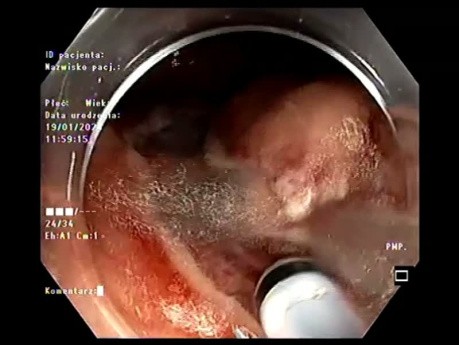

Endoskopowa dyssekcja podśluzówkowa dużego 11x5cm...

Przypadek ponad 80-letniego pacjenta z zespołem słabości, który odmówił leczenia chirurgicznego. Ogromna 11-centrymetrowa polipowata zmiana siedząca typu LST-G - wycięta metodą resekcji w jednym fragmencie...